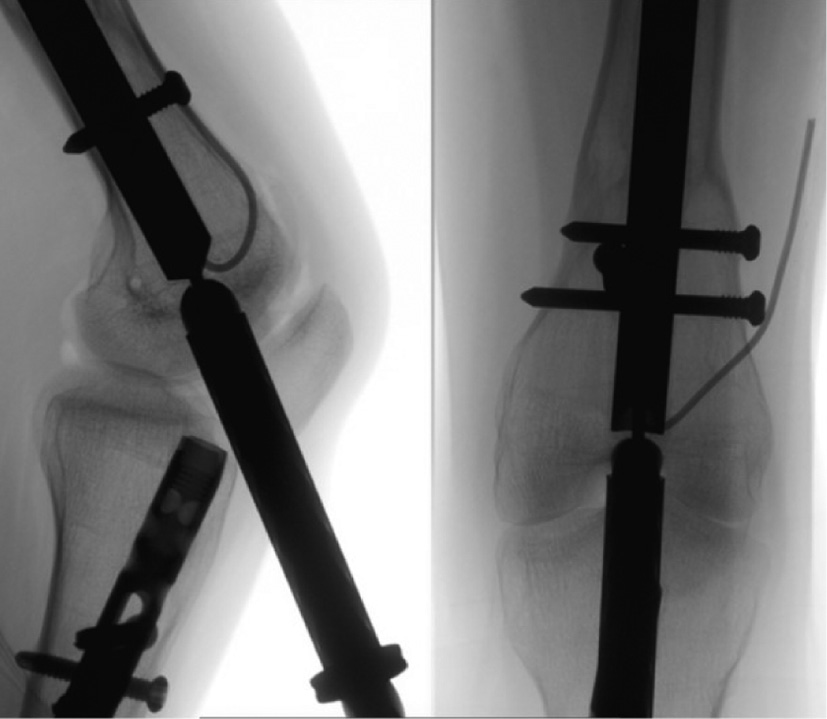

Figure 7a (left) and 7b (right). Carefully advance the guidewire under fluoroscopic guidance into the center of the nail on the anteroposterior view (7a) and the lateral view (7b).

jposna20220031_fig7.jpg